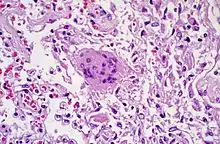

• Fremdkörper-Riesenzellen - Typisch in Fremdkörpergranulomen, die Zellkerne sind in einem Haufen zusammengelagert

• LANGHANS-Riesenzellen - In Tuberkulosegranulomen, die Kerne sind hufeisenförmig angeordnet

• TOUTON-Riesenzelle - Schaumzellen, bei denen um eine kleine schaumfreie Insel mehrere Kerne ringförmig angeordnet sind, Vorkommen z.B. bei juveniler Xanthogranulomatose, siehe Abb.

LANGHANS-Riesenzellen in einem Tbc-Granulom, transbronchiale Biopsie

Fremdkörper-Riesenzellen bei Aspirationspneumonie, Autopsiepräparat, H&E.